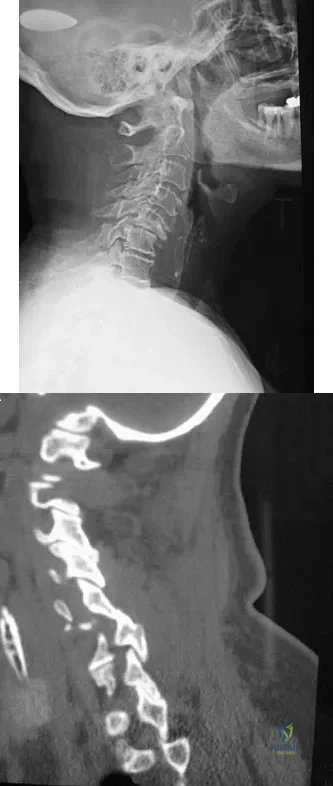

Question 59

A 65-year-old woman has significant neck pain after falling and striking her head. A radiograph and sagittal CT scan are shown in Figures 23a and 23b. What is the most likely diagnosis?

Explanation